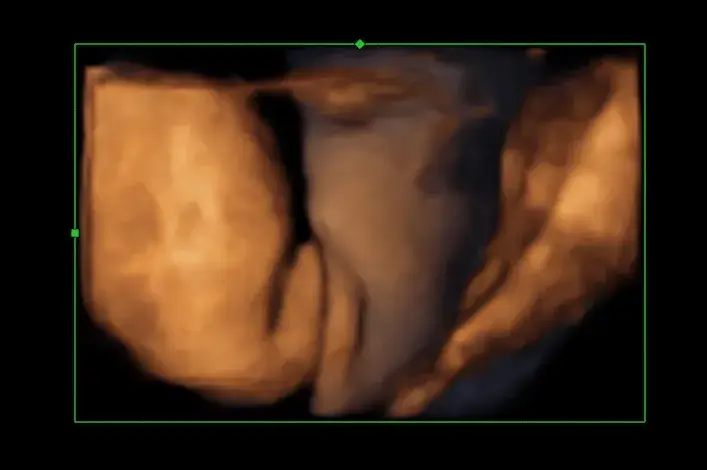

Wybór odpowiedniego sprzętu medycznego ma kluczowe znaczenie dla dokładności ustalania płci dziecka na USG. Istnieje wiele technologii ultrasonograficznych, które różnią się jakością obrazu oraz możliwościami diagnostycznymi. Najpopularniejsze z nich to USG 2D oraz USG 3D. Technologia 2D dostarcza płaskiego obrazu, który jest wystarczający do podstawowej oceny, natomiast 3D oferuje trójwymiarowy obraz, co może ułatwić identyfikację narządów płciowych.

| USG 3D | Zaawansowana technologia, oferująca trójwymiarowe obrazy, lepsza do analizy anatomicznej. | Siemens Acuson S3000, Canon Aplio i900 |